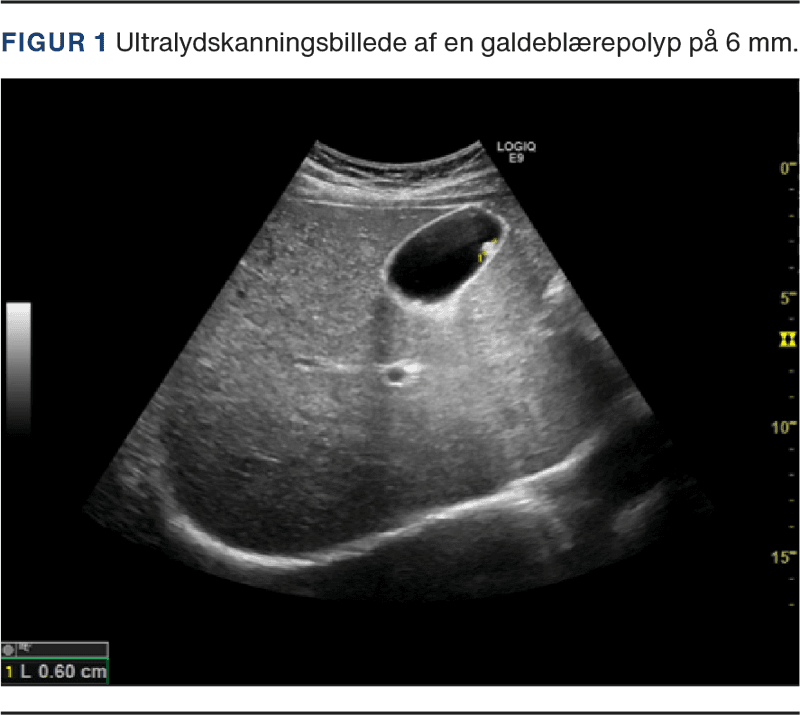

GBP er defineret som en elevation af galdeblærens slimhinde, der prominerer mod lumen uden at kaste slagskygge ved UL-skanning (Figur 1). GBP diagnosticeres oftest som et tilfældigt fund i forbindelse med billeddiagnostiske undersøgelser såsom CT, UL- og MR-skanning eller ved undersøgelse af galdeblærens slimhinde efter kolecystektomi. Der er tale om et hyppigt fund med en prævalens i den globale population på 5-12% [2]. GBP findes tilfældigt i op til 13,8% ved histopatologisk undersøgelse af galdeblæreresektater efter kolecystektomi [3].

Risikofaktorer for GBC ved UL-skanning er solitære polypper, størrelse > 10 mm, sessil (bredbaset) form, samtidig lokalfortykkelse af galdeblærevæggen > 4 mm og/eller opbrydning af den normale lagdeling af galdeblærevæggen (Figur 2). Ved brug af CEUS-skanning og/eller CDI kan øget vaskularisering bestyrke mistanke om malignitet, men ikke bidrage med definitiv diagnose [2] (Figur 2).